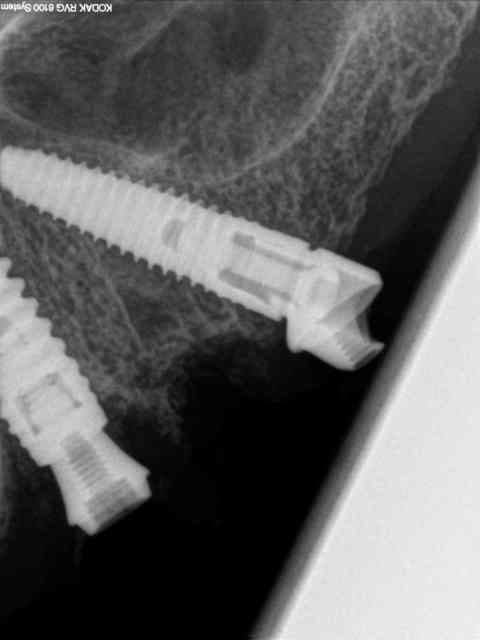

je vous mets les radios per-op.

secteur 1:

à l'aide du guide je détermine la position et l'axe de l'implant.

retrait du guide et contrôle radio puis pose des implants

secteur 2:

on voit bien ici que cette méthode reste suffisamment précise pour longer le sinus sans le pénétrer.

je n'en demande pas d'avantage.

Cet implant pénètre de 5 à 6 mm dans le sinus.